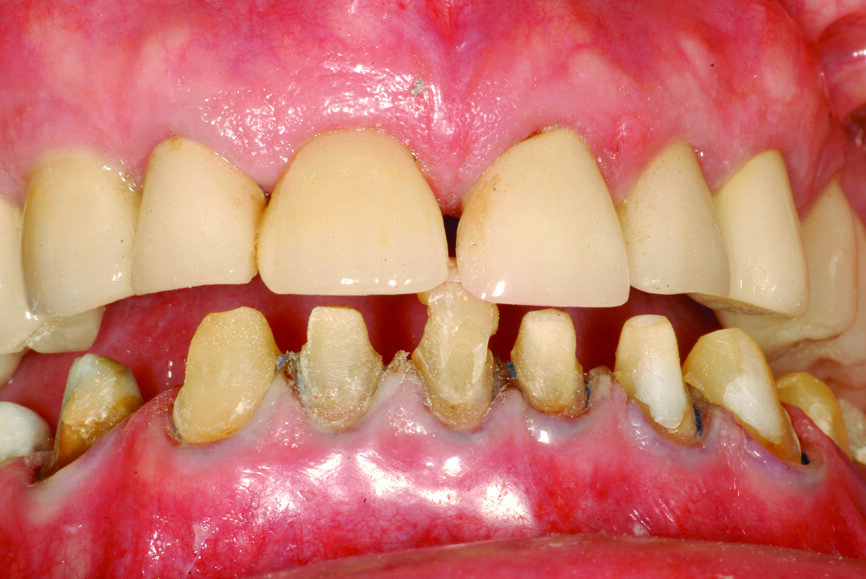

Fig. 13: Intercuspation requiring opening of the vertical dimension for restorative space.

Fig. 14: Significant wear requiring occlusal coverage and altering

of occlusion.

Fig. 15: Occlusion with the mandible in centric relation and a significant open bite.

Fig. 16: Occlusion with intercuspation but a non-functional

mandibular position.